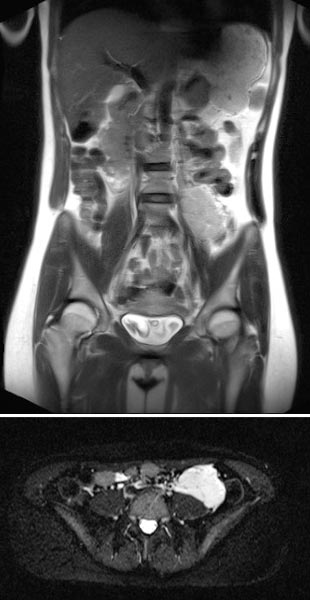

Coronal (top) and axial (bottom) T2-weighted sequences without contrast at 21 weeks' gestation.

Marked increase in size of the VM during pregnancy, which is visualized ventrally of the left psoas muscle as a signal-intense lesion, without displacement or compression of the placenta.

Coronal T2 sequences depicting progression of the VM ventrally sitting on the left psoas muscle at 21 weeks’ gestation. During pregnancy, the patient also develops grade 3 right-sided hydronephrosis.

In the axial T2-HASTE sequence at 21 weeks' gestation, the VM is adjacent to the placenta without displacement of the uterus or fetus.